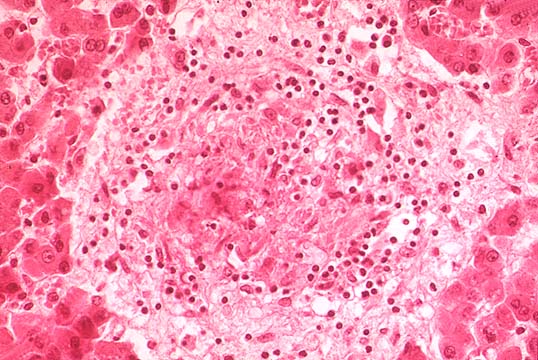

Salmonellosis

Fig.142-Salmonellosis

The illustration shows a granuloma produced by Salmonella typhi, the typhoid nodule, which consists of an intra parenchymal focus of necrosis with histiocytes, some neutrophils an will contain the gram negative organisms.